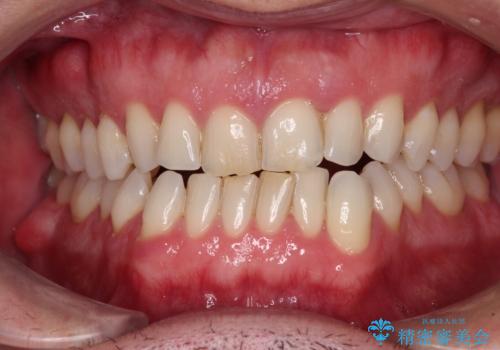

[ 前歯開咬 ] 前歯が噛んでいない マウスピース矯正治療

担当医 大元洋佑

![[ 前歯開咬 ] 前歯が噛んでいない マウスピース矯正治療の症例 治療前](https://seimitsushinbi.jp/wp/wp-content/uploads/2022/11/IMG_4669-500x350.jpg?v=1668218426)

![[ 前歯開咬 ] 前歯が噛んでいない マウスピース矯正治療の症例 治療後](https://seimitsushinbi.jp/wp/wp-content/uploads/2022/11/IMG_2488-500x350.jpg?v=1668218373)